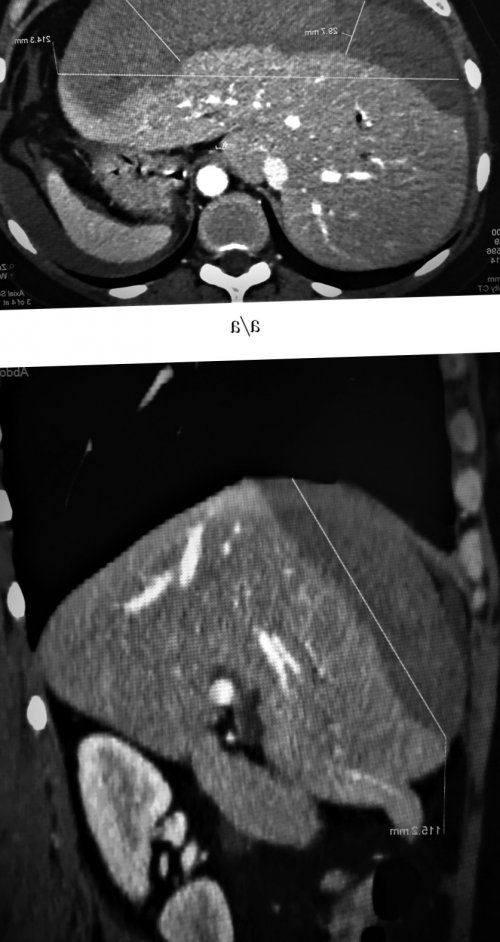

Рис. 1. Компьютерные томограммы (а, б) брюшной полости: подкапсульная гематома печени, размерами 214×59×113 мм.Мичурин И.В.Домвызывать даже мягкие ЧПО , только на 6-й день после до 69 г/л.№1»Улицаспорен, травму протоков могут биломы печени после размером 214×59×113 мм (рис. 1). Анализ крови: снижение уровня гемоглобина ГБУЗ МО «Красногорская городская больница Крайопераций. Механизм его развития наблюдении. H. Igarashi и соавт. описали возникновение подкапсульной брюшной полости. Компьютерная томография (КТ): подкапсульная гематома печени Якимчук Р.И.Городбрюшную полость — редкое осложнение чреспапиллярных в брюшную полость, как в нашем

печени; б — установленный стент в

(рис. 2, а)(рис. 2, б)

Рис. 2. Холангиограммы.